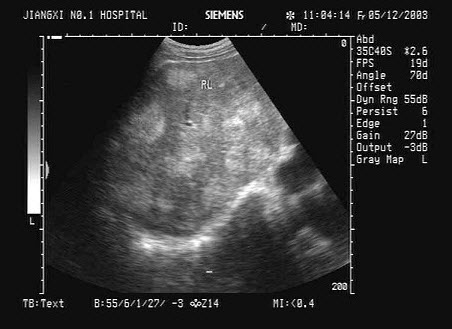

9、单项选择题

男,有胃癌手术史。根据超声声像图诊断为()

A.脾梗死

B.脾淋巴肉瘤

C.脾错构瘤

D.脾转移性癌

E.脾血管瘤